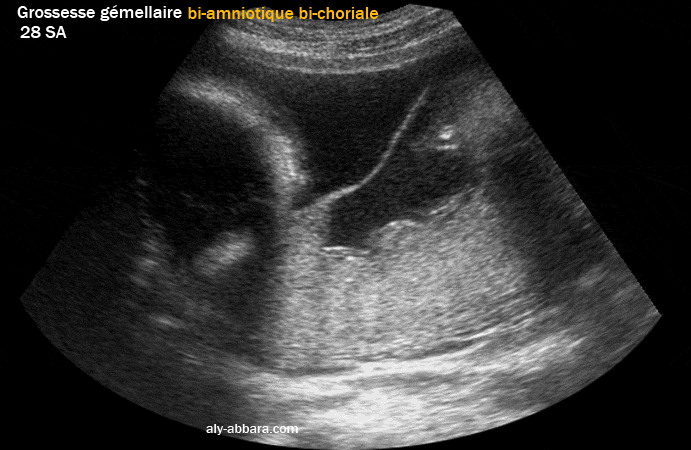

• Image échographique montrant le type de placentation d'une grossesse gémellaire bi-amniotique bi-choriale obtenue par fécondation in vitro (faux jumeaux).

• la cloison séparant les deux cavités ovulaires (cloison inter-ovulaire) est composée des deux amnios en dehors et des deux chorions au centre.

• Le raccordement de la membrane inter-ovulaire au niveau de la paroi utérine prend l'aspect de " λ " ; ce raccordement est connu sous le nom du signe Lambda (au premier trimestre de la grossesse) et le signe de Twin Peak (au 2e et 3e trimestres de la grossesse).

• Cette forme de placentation (bi-choriale ; bi-amniotique) se voit dans toutes les grossesses gémellaires dizygotes (faux jumeaux) et dans 30 % des grossesses gémellaires monozygotes (vrais jumeaux).